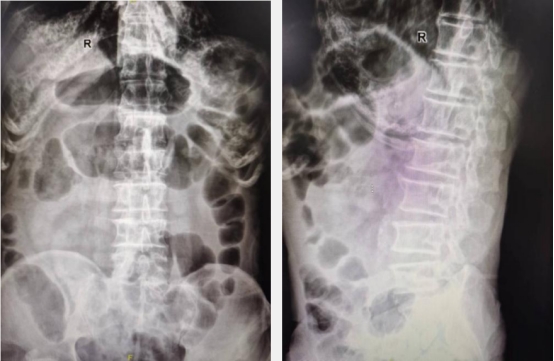

影像学检查示L2腰椎椎体新鲜压缩性骨折

患者来院后行腰椎X线检查,未见明显骨折表现,但考虑到患者腰部剧烈疼痛,且骨质疏松,很有可能发生了骨松性病理性骨折,进一步行腰椎核磁检查,发现患者腰椎压缩性骨折,并伴有轻度腰椎后凸畸形。王岩松教授,程道林主治医师经过详细询问病史、系统体格检查,辅以各项影像学检查,确诊患者为腰椎L2椎体压缩性骨折。王岩松告诉患者家属,传统的治疗方式是通过腰后路开放手术,置入腰椎后路钉棒系统,达到恢复骨折椎体高度,恢复腰椎整体即刻稳定性的目的。但患者90岁高龄,且合并慢性阻塞性肺疾病、肺气肿、冠心病等多种基础疾病。该手术方式需要在全麻下进行,手术创伤相对较大,存在较高风险。若行保守治疗则需要严格卧床至少3个月,但长期卧床会导致患者骨量流失,每卧床一周骨量就会减少1%,而且长期卧床还会导致压疮、坠积性肺炎、尿路感染等严重卧床并发症,对老人的生命造成极大威胁。